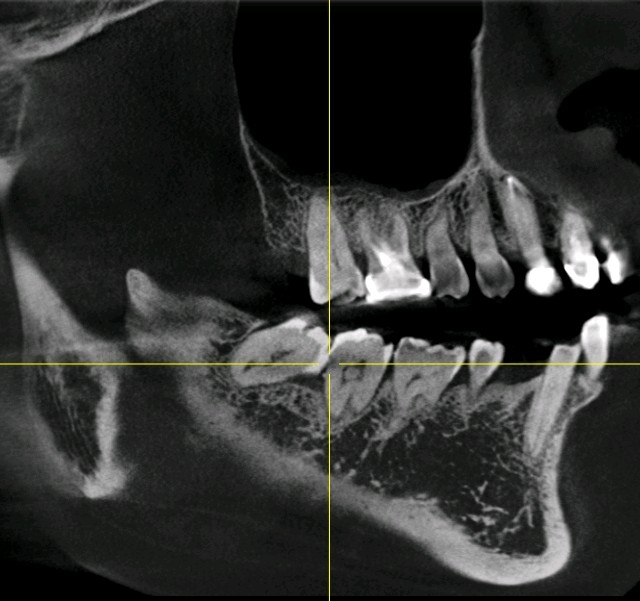

那么一般什么样的智齿需要拔除呢?1、阻生齿或和相邻磨牙接触不正常的智齿。2、咬腮智齿3、对颌没有牙,没有咬合功能的智齿。4、智齿本身存在牙体疾病。

对于以上这些智齿如果不拔除会有哪些危害呢?1、会顶坏邻近牙齿。常常塞牙导致邻牙龋坏或者牙槽骨吸收。2、容易引起智齿冠周炎。智齿萌出不全异位或者阻生。牙龈与牙体之间容易形成一个狭窄较深的盲袋。易积攒食物残渣滋生细菌。时间长了就会造成智齿冠周炎起疼痛,肿胀,张口受限,严重了会导致间隙感染。3、影响咬合。智齿萌出位置异常,导致咬合关系错乱,影响颞下颌关节的正常活动。4、位置靠后不易清洁,食物残渣堆积容易发生龋坏,长期以往会发展成牙髓炎,发生疼痛的现象。